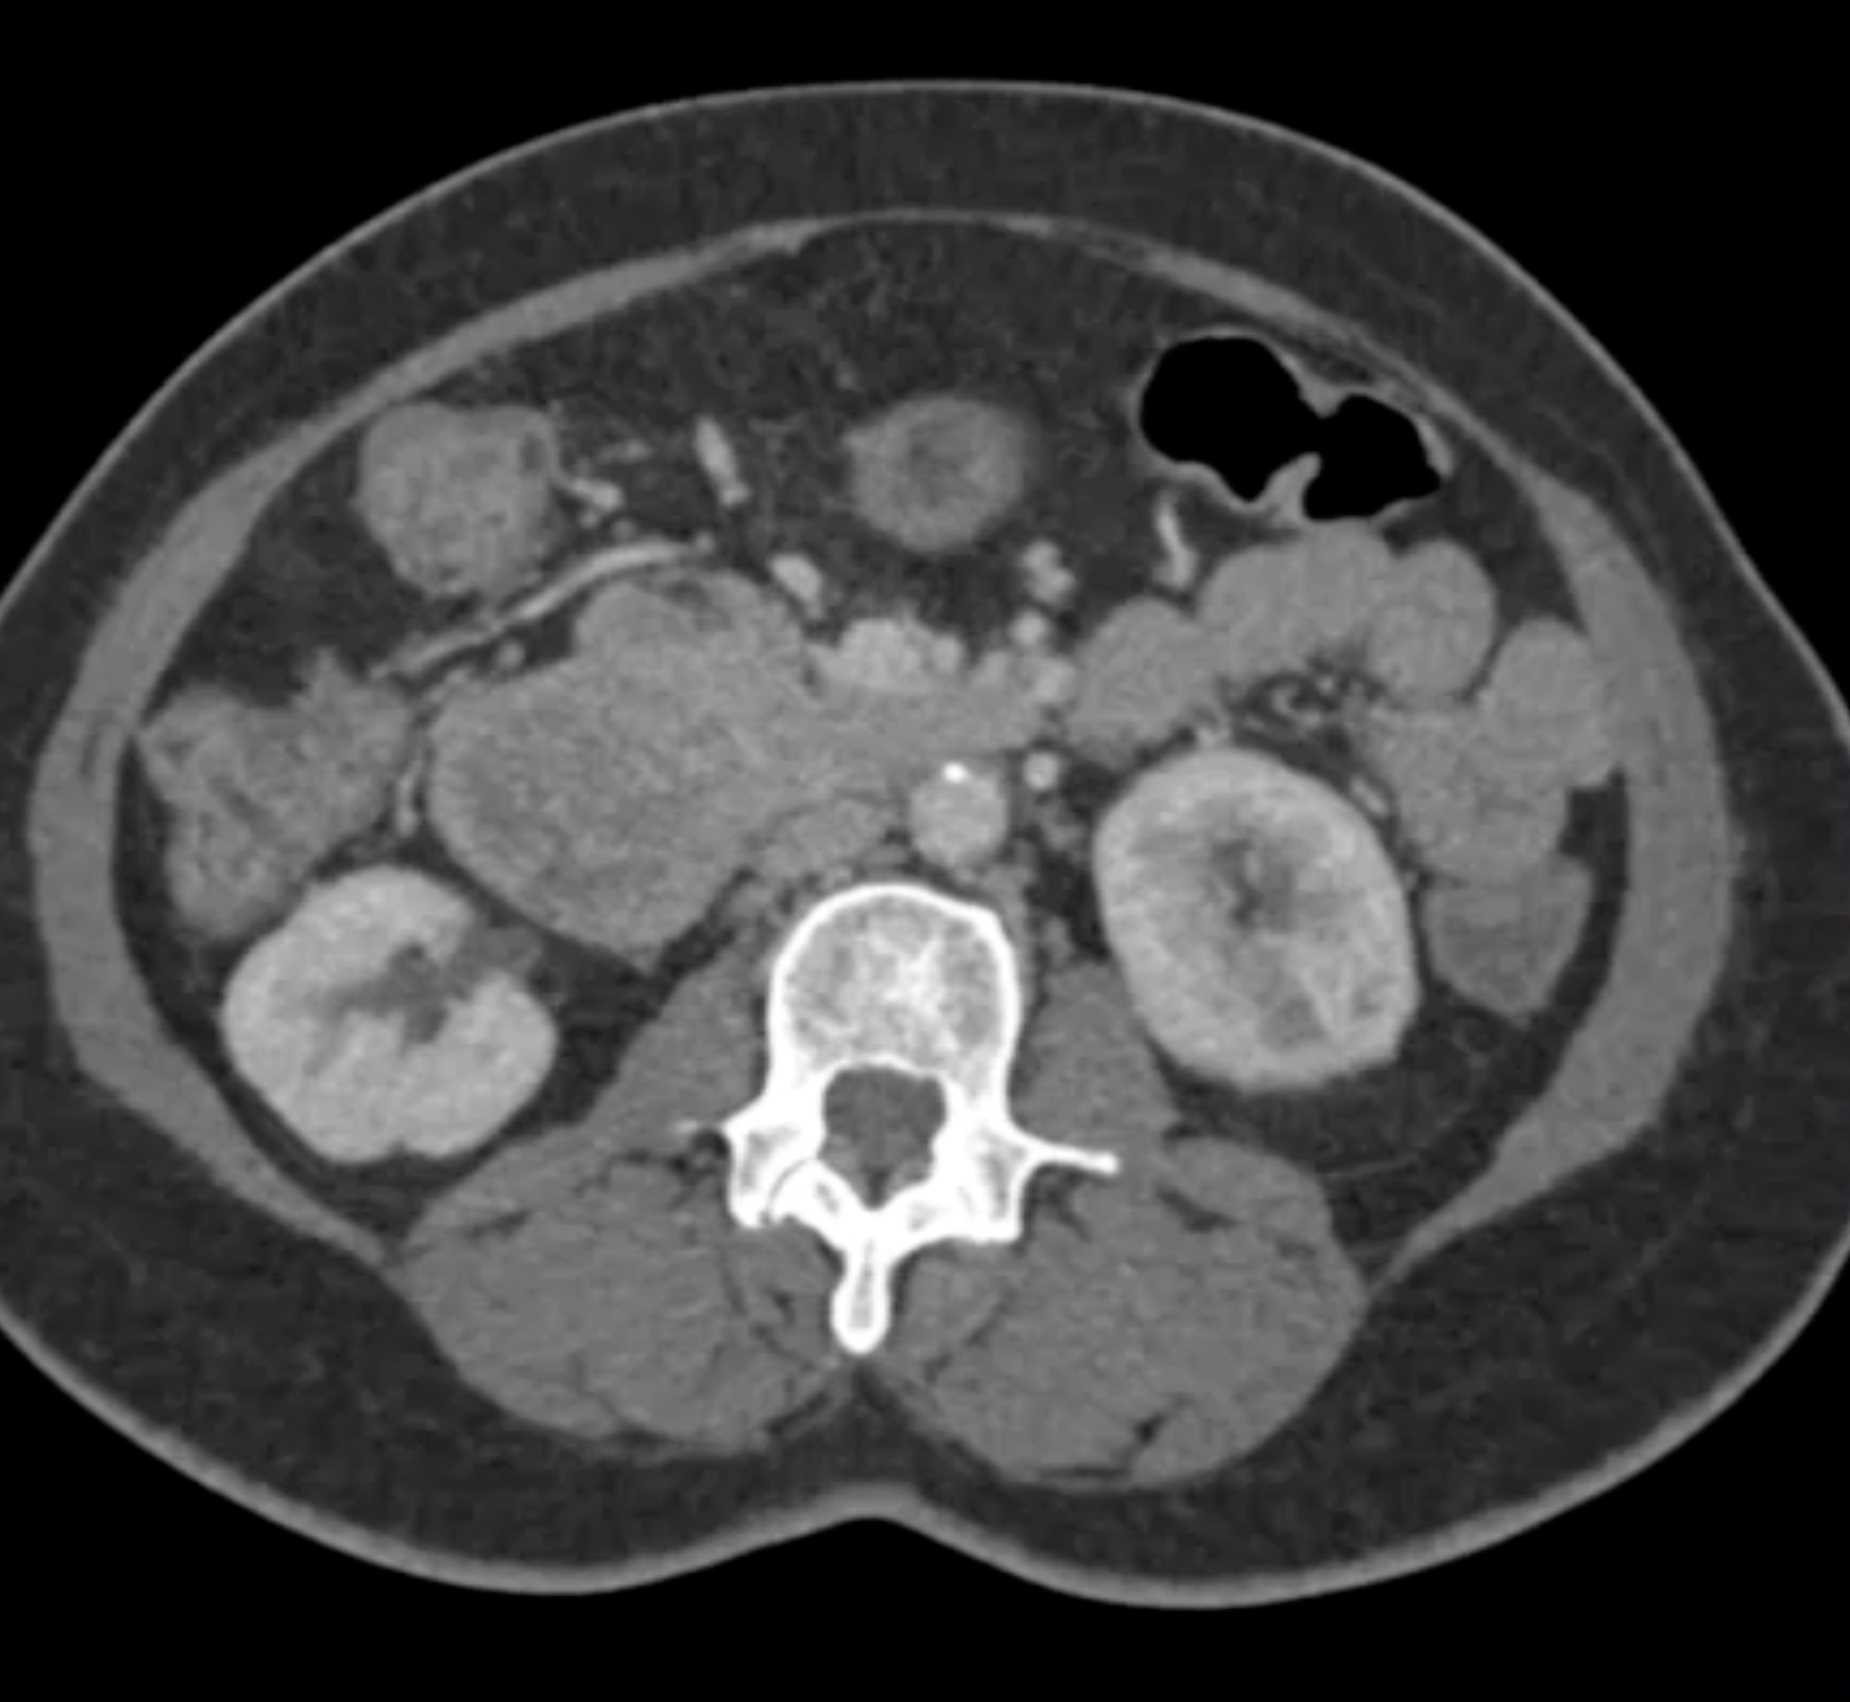

Lagre Gastric GIST Tumor